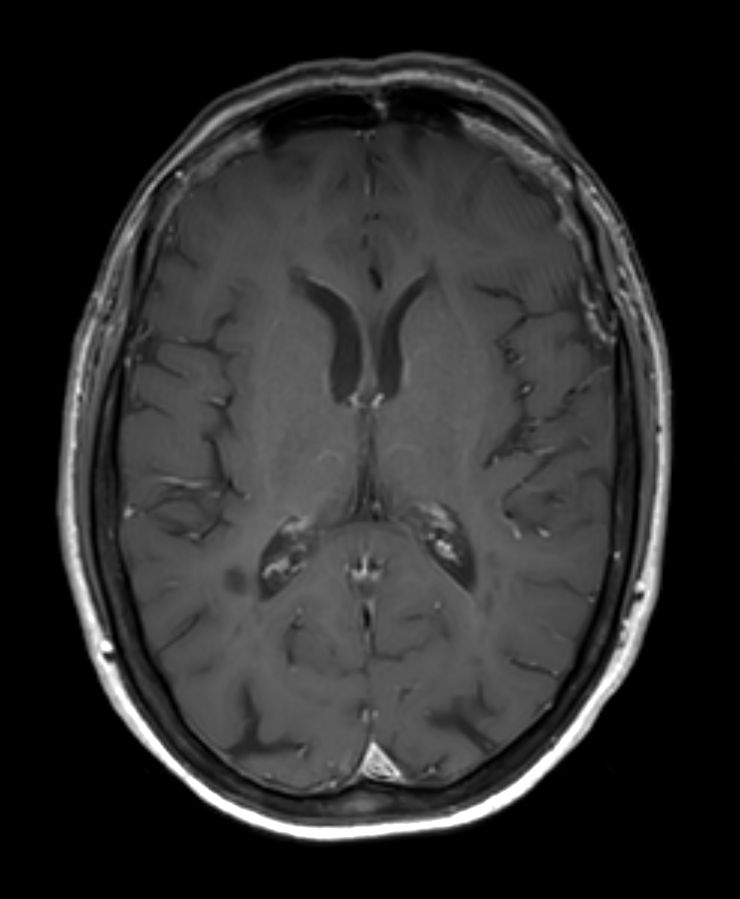

3D T1w FFE +Gado Compressed SENSE

3D T1w FFE (reformat) +Gado Compressed SENSE